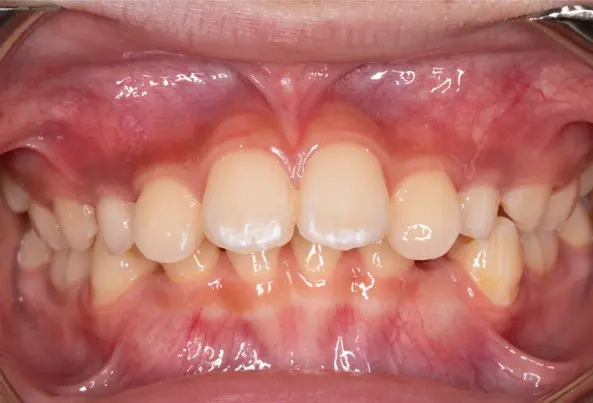

Before

After